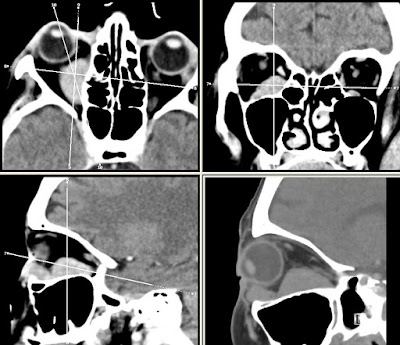

Szerző: admin | júl 6, 2011 | Oncohaematology, Orbita

3292782011.06.14